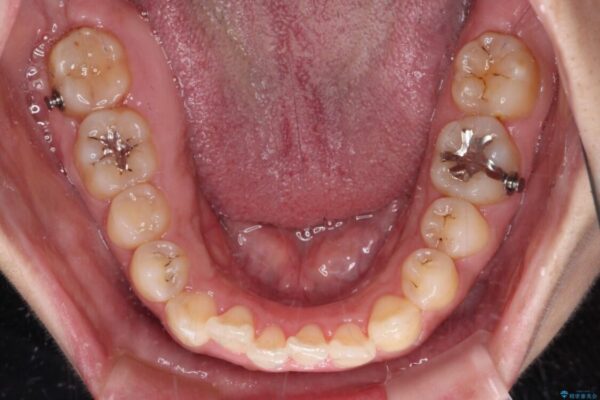

治療途中

• 【モニター】カリエール・ディスタライザーを併用した八重歯のインビザライン矯正 治療途中画像

インビザライン単体で改善することも可能ですが、八重歯とその後方にある歯列を確実移動させないと、上下正中がずれてしまう可能性があります。

インビザライン単体での治療ではなく、カリエール・ディスタライザーという補助装置を併用して、より確実性を上げることとしました。

補助装置で八重歯を解消しながら、並行してインビザラインで歯列を整えることとしました。